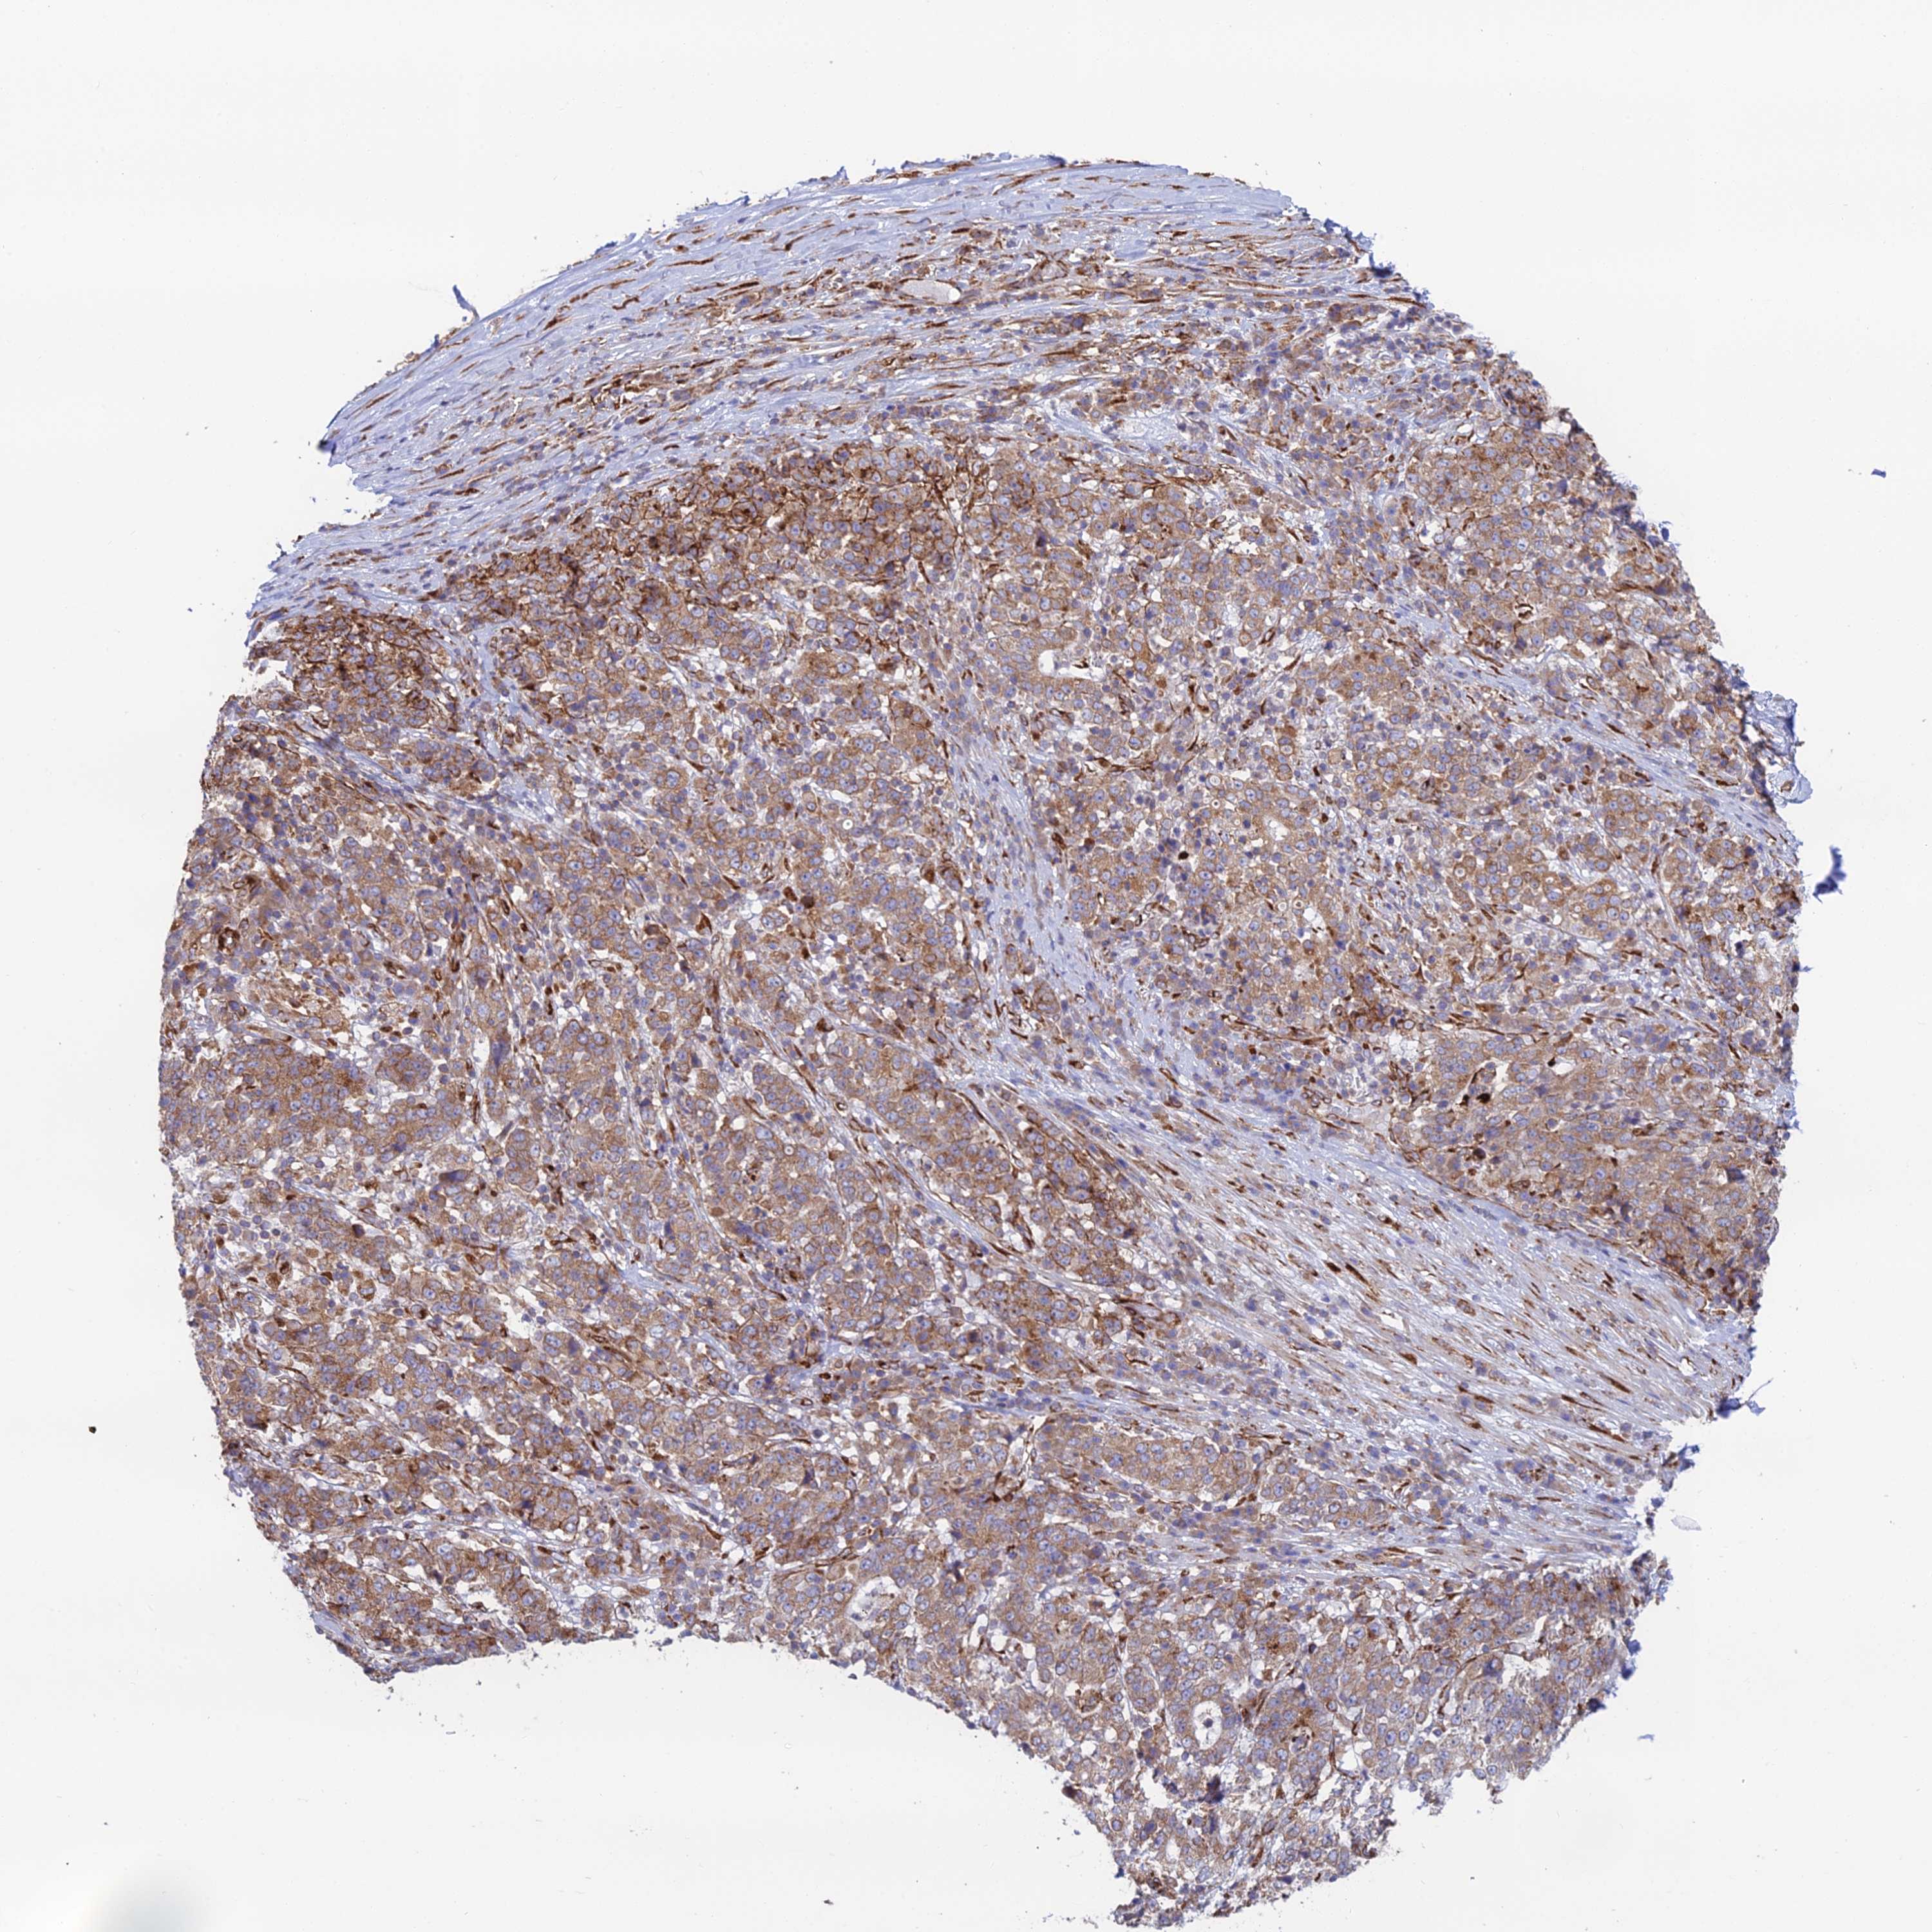

STOMACH CANCER - Protein expressioni

A mouse-over function shows sample information and annotation data. Click on an image to view it in a full screen mode. Samples can be filtered based on level of antibody staining by selecting one or several of the following categories: high, medium, low and not detected. The assay and annotation is described here.

Antibody stainingi

Antibody staining in the annotated cell types in the current human tissue is reported as not detected, low, medium, or high, based on conventional immunohistochemistry profiling in selected tissues. This score is based on the combination of the staining intensity and fraction of stained cells.

Each image is clickable and will lead to virtual microscopy that enables deeper exploration of all samples and also displays staining intensity scores, fraction scores and subcellular localization as well as patient and tissue information for each sample.

Antibody HPA043648

Staining

High

Medium

Low

Not detected

Intensity

Strong

Moderate

Weak

Negative

Quantity

>75%

75%-25%

<25%

None

Location

Nuclear

Cytoplasmic/membranous

Cytoplasmic/membranous,nuclear

Adenocarcinoma, NOS